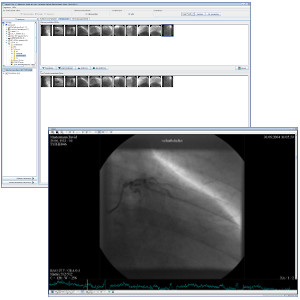

TM-PACS

Het maakt de compressie, beveiliging, opslag en visualisatie van radiologische beelden mogelijk met tools voor gerichte weergave en visualisatie (zoom, vergrootglas, annotaties, afstandmeting, opvolging van metingen, enz.). De gebruiker kan zo tegelijkertijd beelden van coronarografie, PET-beelden uit de nucleaire geneeskunde en meer klassiek beeldmateriaal (NRM, CT Scan, echographie, enz.) visualiseren. Het gebruik van onderzoeksgerelateerde labels maakt het mogelijk onderzoeksgroepen samen te stellen en die met één enkele klik te openen. Een gepersonaliseerd zoeksysteem maakt het mogelijk het patiëntdossier of het gewenste onderzoek zeer snel te vinden. Het beeldscherm is geoptimaliseerd zodat weergave op meerdere schermen mogelijk is. Hierbij mogen we ook de integratie van de RIS- en PACS-software die op dezelfde diagnosestations worden geïnstalleerd, niet vergeten.